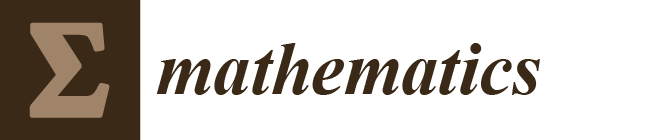

- We propose to use multiple slices as input that include neighboring slices, to extract correlated information from them.

2.2. Method

2.2.1. Parallel UNet